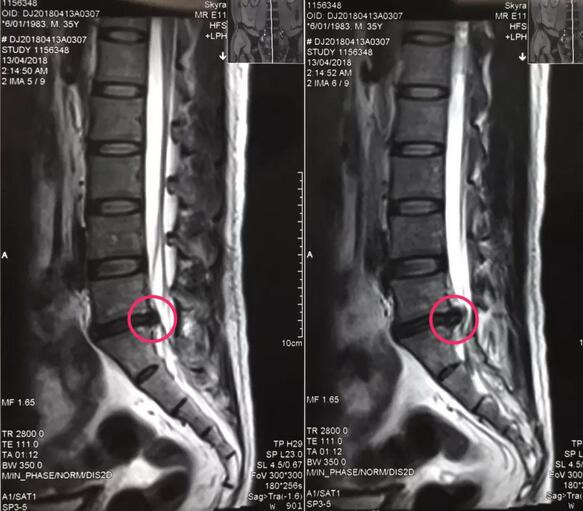

近日,21点玩法研究所 骨一科为一名卧床四个月的患者成功实施了经皮椎间孔镜下髓核摘除术,手术效果良好,患者术后即可下地走路。

八零后李先生来自山西长治,是家里的顶梁柱,半年前开始出现腰痛不适,工作繁忙没有时间看病,后来突然加重并出现左下肢放射样抽痛,走路都走不了,在当地多家21点游戏规则 检查确诊为腰椎间盘突出症,治疗方案都是开刀手术,打钉固定,小李拒绝开放手术,回家卧床四个多月,仍然不能下地走路,亲朋友好友四处寻医问药,终于从病友群里打听到,21点玩法研究所 可以微创手术,效果很好,就专程前来。骨一科专家团队给李先生进行了详细的查体和认真的读片,告诉李先生诊断确实是腰椎间盘突出症,适合孔镜微创,不用开放手术,不用打钉固定,李先生欣然接受。7月27日,骨一科微创团队为李先生实施了经皮椎间孔镜下髓核摘除术,手术一小时,术后下肢抽痛症状完全解除,终于可以下地走路了,李先生和家人对手术效果非常满意。